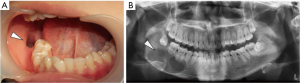

First, for the preparation of the drainage plug mold, the range and shape of the cyst cavity were determined using a panoramic X-ray, and the range of cyst invasion was analyzed in 3D (16). The spatial structure of the cyst cavity was reconstructed using 3D printing (Figure 1A,B). The plug mold, which was adapted to the cyst cavity, was constructed in combination with 3D printing technology (17).